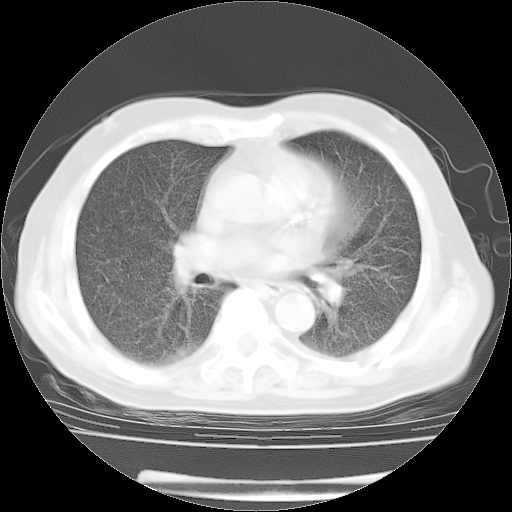

4月28日肺部CT——再次出现类似去年5月9日——透光度降低,“间质性”改变。

4月28日肺部CT——再次出现类似去年5月9日——磨玻璃样、间有“粟粒样”改变。

个人阅读4.14日肺部CT平扫:纵隔窗无异常,但肺窗示:双下肺内、后基底段有片絮状侵润影,部位以后基底段为著,以间质改变为主,呈急性肺泡炎征像,和首次住院影像学有相似之处。仅是个人读片,明日请相关专家再读片哈。其它建议同上。